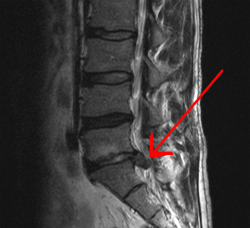

Este disco, presenta en su anatomía una zona central pulposa, llamada Núcleo pulposo y alrededor un Anillo fibroso, cuando el disco se comprime entre las dos vértebras y toca o rechaza el saco dural, estamos hablando de una protusión que puede ser posterior, central o lateral. Si por el contrario éste anillo fibroso se rompe y sale este núcleo pulposo hacia el canal contactando con el saco dural, estamos en presencia de una hernia discal.